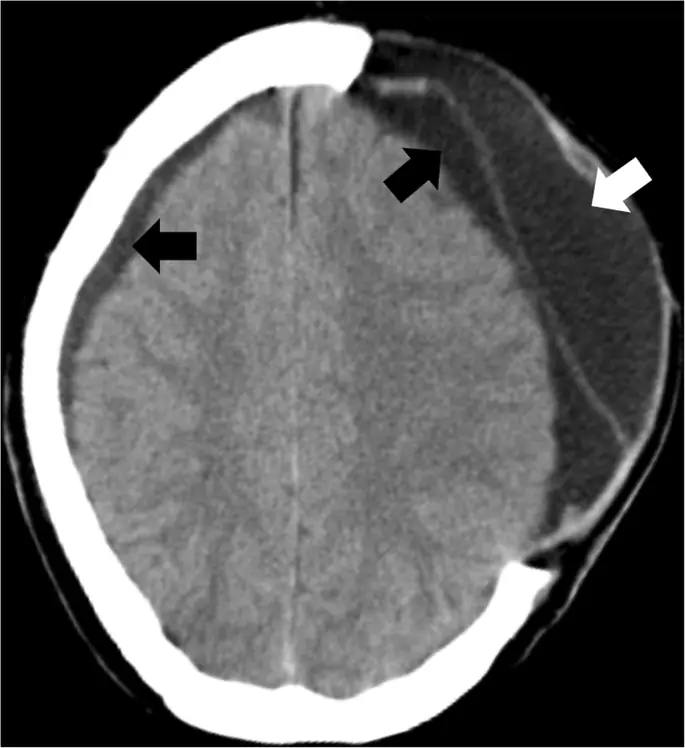

Долгосрочным осложнением после ДК является синдром синдрома трепанного или затонувшего кожного лоскута, который возникает от нескольких недель до месяцев после ДК и часто характеризуется неврологическим ухудшением после начальных реабилитационных улучшений (58). Очевидным результатом клинических и рентгенологических исследований больных пациентов является сильно утопленный клапан раковины, перекрывающий дефект краниэктомии (рис. 9), который еще более очевиден в вертикальном положении и может усугубляться диверсией CSF или значительной атрофией инфарктной территории., Патофизиология этого синдрома, по-видимому, представляет собой несоответствие между атмосферным давлением и внутричерепным давлением, что приводит к нарушению церебральной перфузии, венозного оттока и динамики CSF. Подавляющее большинство случаев значительно улучшится после краниопластики (58).

figure9

Затонувший кожный лоскут после ДК. Осевая компьютерная томография, показывающая затонувший кожный лоскут (белая стрелка) после левосторонней гемикраниэктомии

Изображение в полном размере